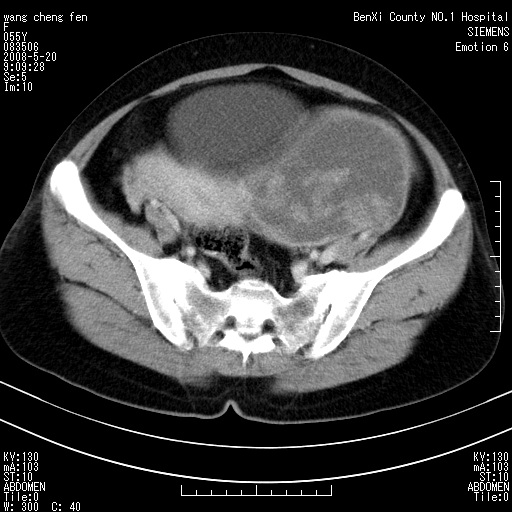

女、绝经后阴道流血3个月

左侧附件区巨大囊实性病灶,边缘光整,病灶囊壁较厚,增强示囊壁及实性部分明显强化,强化呈度与宫体实质大致相同,宫腔积液征像,未见盆腔积液等其他异常,考虑左侧卵巢囊腺癌,不除外囊腺瘤及浆膜下肌瘤坏死

左侧附件区巨大囊实性病灶,边缘光整,病灶囊壁较厚,增强示囊壁及实性部分明显强化,强化呈度与宫体实质大致相同,宫腔积液征像,未见盆腔积液等其他异常。绝经后阴道流血3个月,结合病史左侧卵巢囊腺癌首先考虑,宫腔扩大不除外累及。期待结果。

缺延时片子,左侧盆腔囊实性占位,来自于左侧附件可能性大,囊腺癌可能性大。

囊实性肿块分隔厚度较大,厚薄不均,增强实性成分明显强化,有不规则阴道流血,卵巢囊腺癌可能性大。